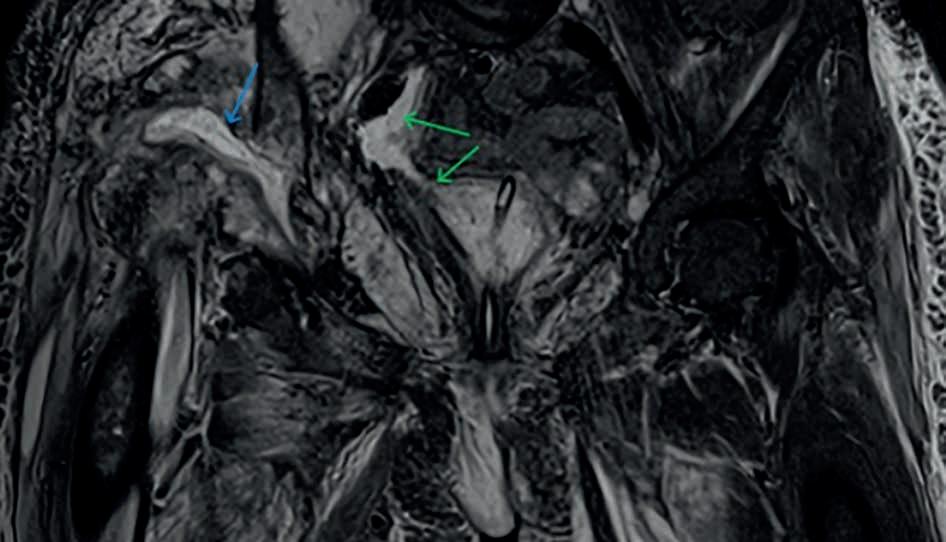

przeciekanie moczu z pęcherza do zaślepionego fragmentu jelita grubego. W badaniu rezonansu magnetycznego z początku grudnia 2023 r. zaobserwowano masywne obrzęki grup mięśniowych okolicy stawu biodrowego po stronie prawej i lewej, spowodowane naciekami płynowymi. Co więcej, potwierdzono komunikację płynu między prawym stawem biodrowym a ,,kloaką” (ryc. 5.–7.). Podczas hospitalizacji chora wielokrotnie miała nawroty krwawień z pochwy, urostomii, cewki moczowej oraz odbytu, co wpływało na okresowe zwiększenia stężenia CRP i pogorszenie stanu ogólnego.

Rycina 5. Rezonans magnetyczny, obraz T2-zależny: obecne kolekcje płynowe w pochwie (zielona strzałka), ślepo zakończonej odbytnicy (niebieska strzałka) oraz wokół pęcherza moczowego (fioletowa strzałka).

Rycina 6. Rezonans magnetyczny, obraz T2-zależny: widoczne cechy komunikacji pomiędzy zbiornikami płynu okolicy ,,kloaki” i stawem biodrowym prawym.